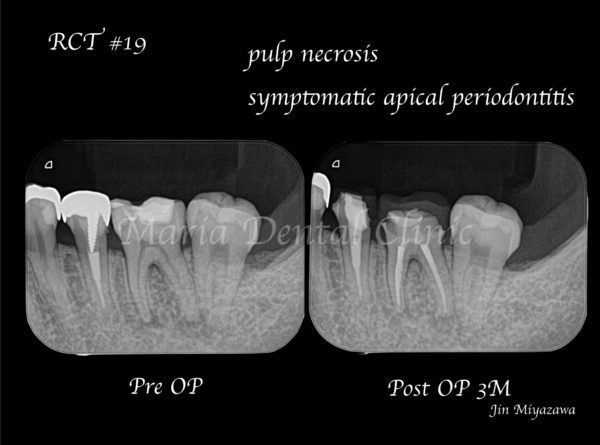

当院での診査の結果、歯髄壊死・根尖性歯周炎と診断しました。カウンセリング当日は痛みが非常に強かったため応急処置まで進め、残りの治療は精密根管治療で行うことになりました。

治療終了後、良好に根の中にバイオセラミックが充填され封鎖できていることを確認し(画像A)、3ヶ月後の経過観察にて、痛みや違和感がないことはもちろんのこと、術前、術後に確認できていた根尖性歯周炎の透過像の縮小を確認(画像B)し経過が良好であると判断しました。